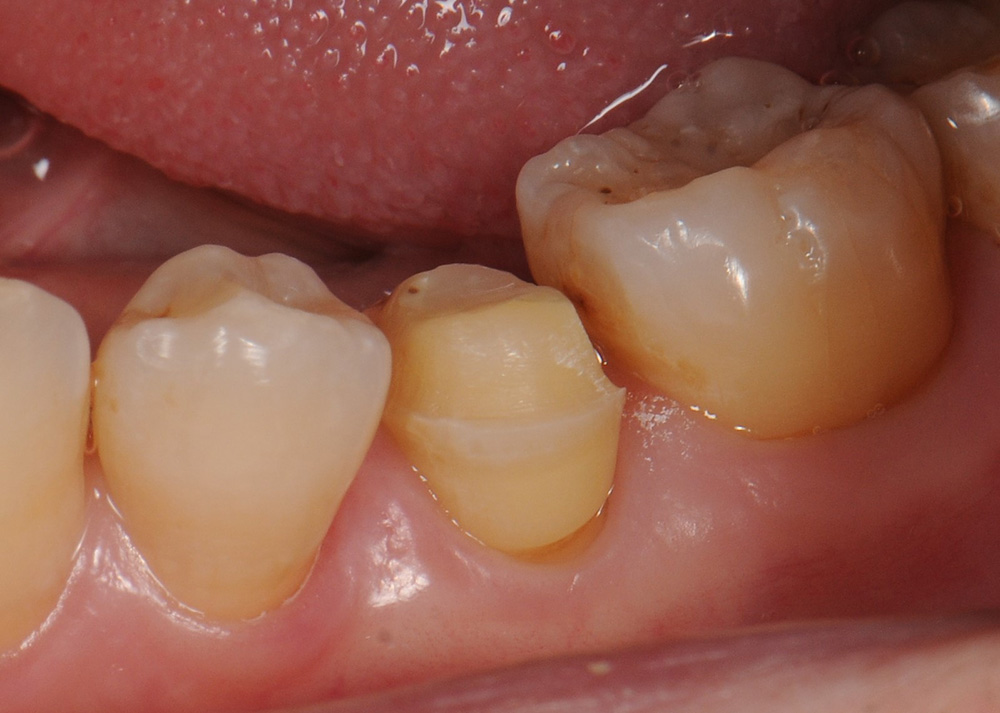

case10 症例(セラミックアンレー)

治療前

| 費用(税込み) | 132,000円 |

| メリット・デメリット | メリット 健全な歯質を削る量が少ない デメリット 歯質を削合する必要がある |

| 治療回数 | 3回(根管治療は別) |

| 主訴 | 奥歯が欠けた |